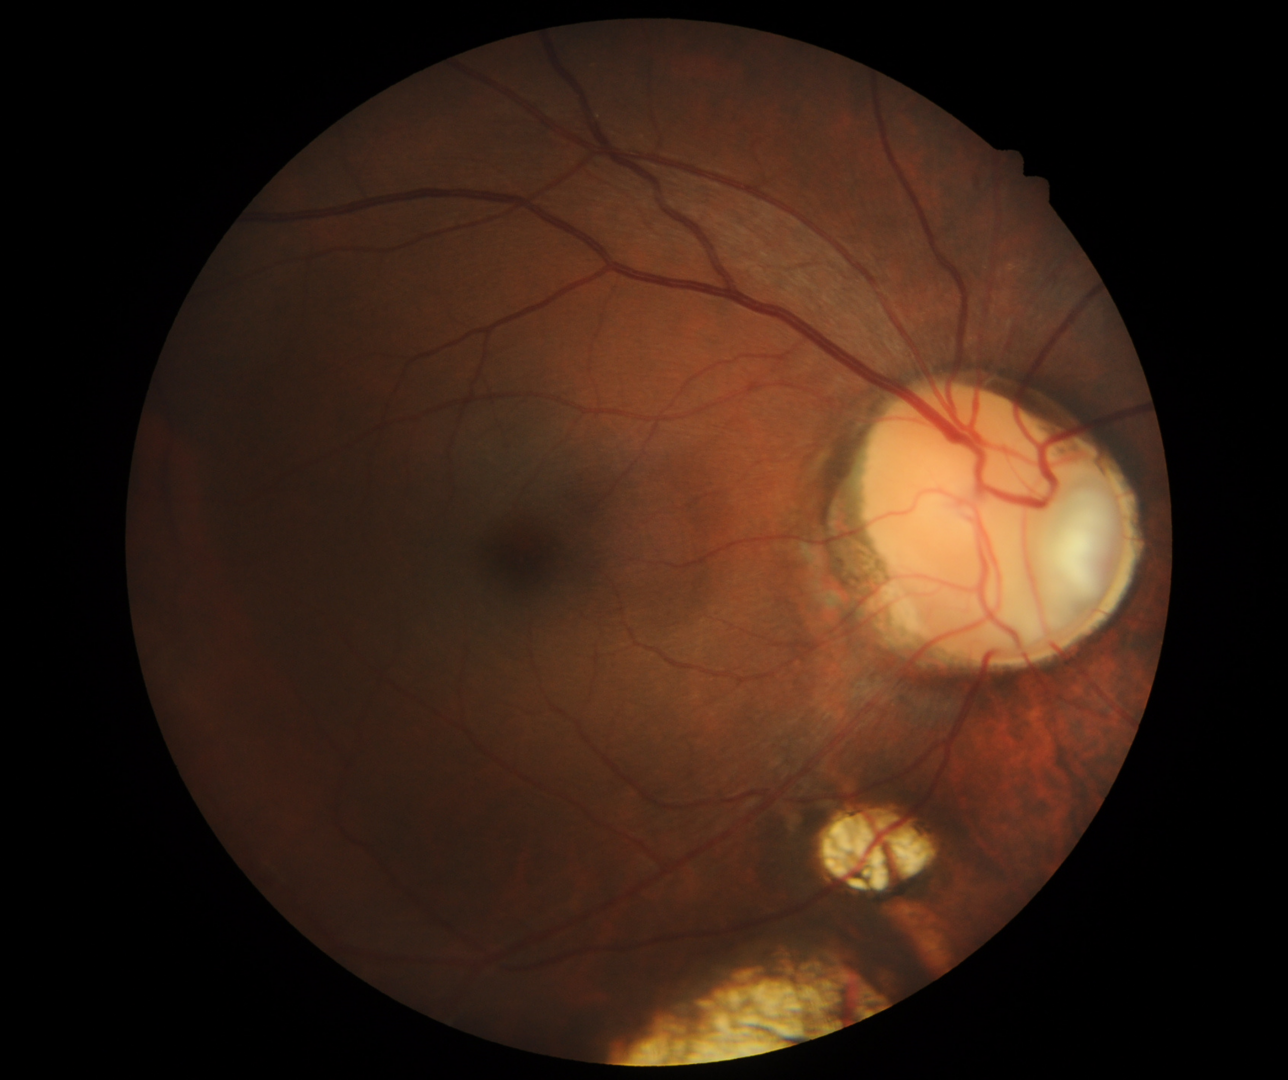

An optic disc coloboma is characterised by a yellow white bowl-shaped excavation of the optic nerve, typically affecting the inferonasal part of the nerve, but in some cases involving the entire disc. Often associated with an optic disc coloboma are chorioretinal colobomas. These are typically found in the inferior retina and have a yellow-white appearance, often with hyperpigmented margins. OCT imaging shows excavation of the retinal and choroidal layers.

A 43 year old Asian male with best corrected visual acuity in the left eye of 6/6 (20/20). Visual field testing revealed a superior absolute field defect corresponding to the areas of coloboma.

Fundus photograph (left eye)

More infoFundus photograph of the optic disc coloboma (left eye)